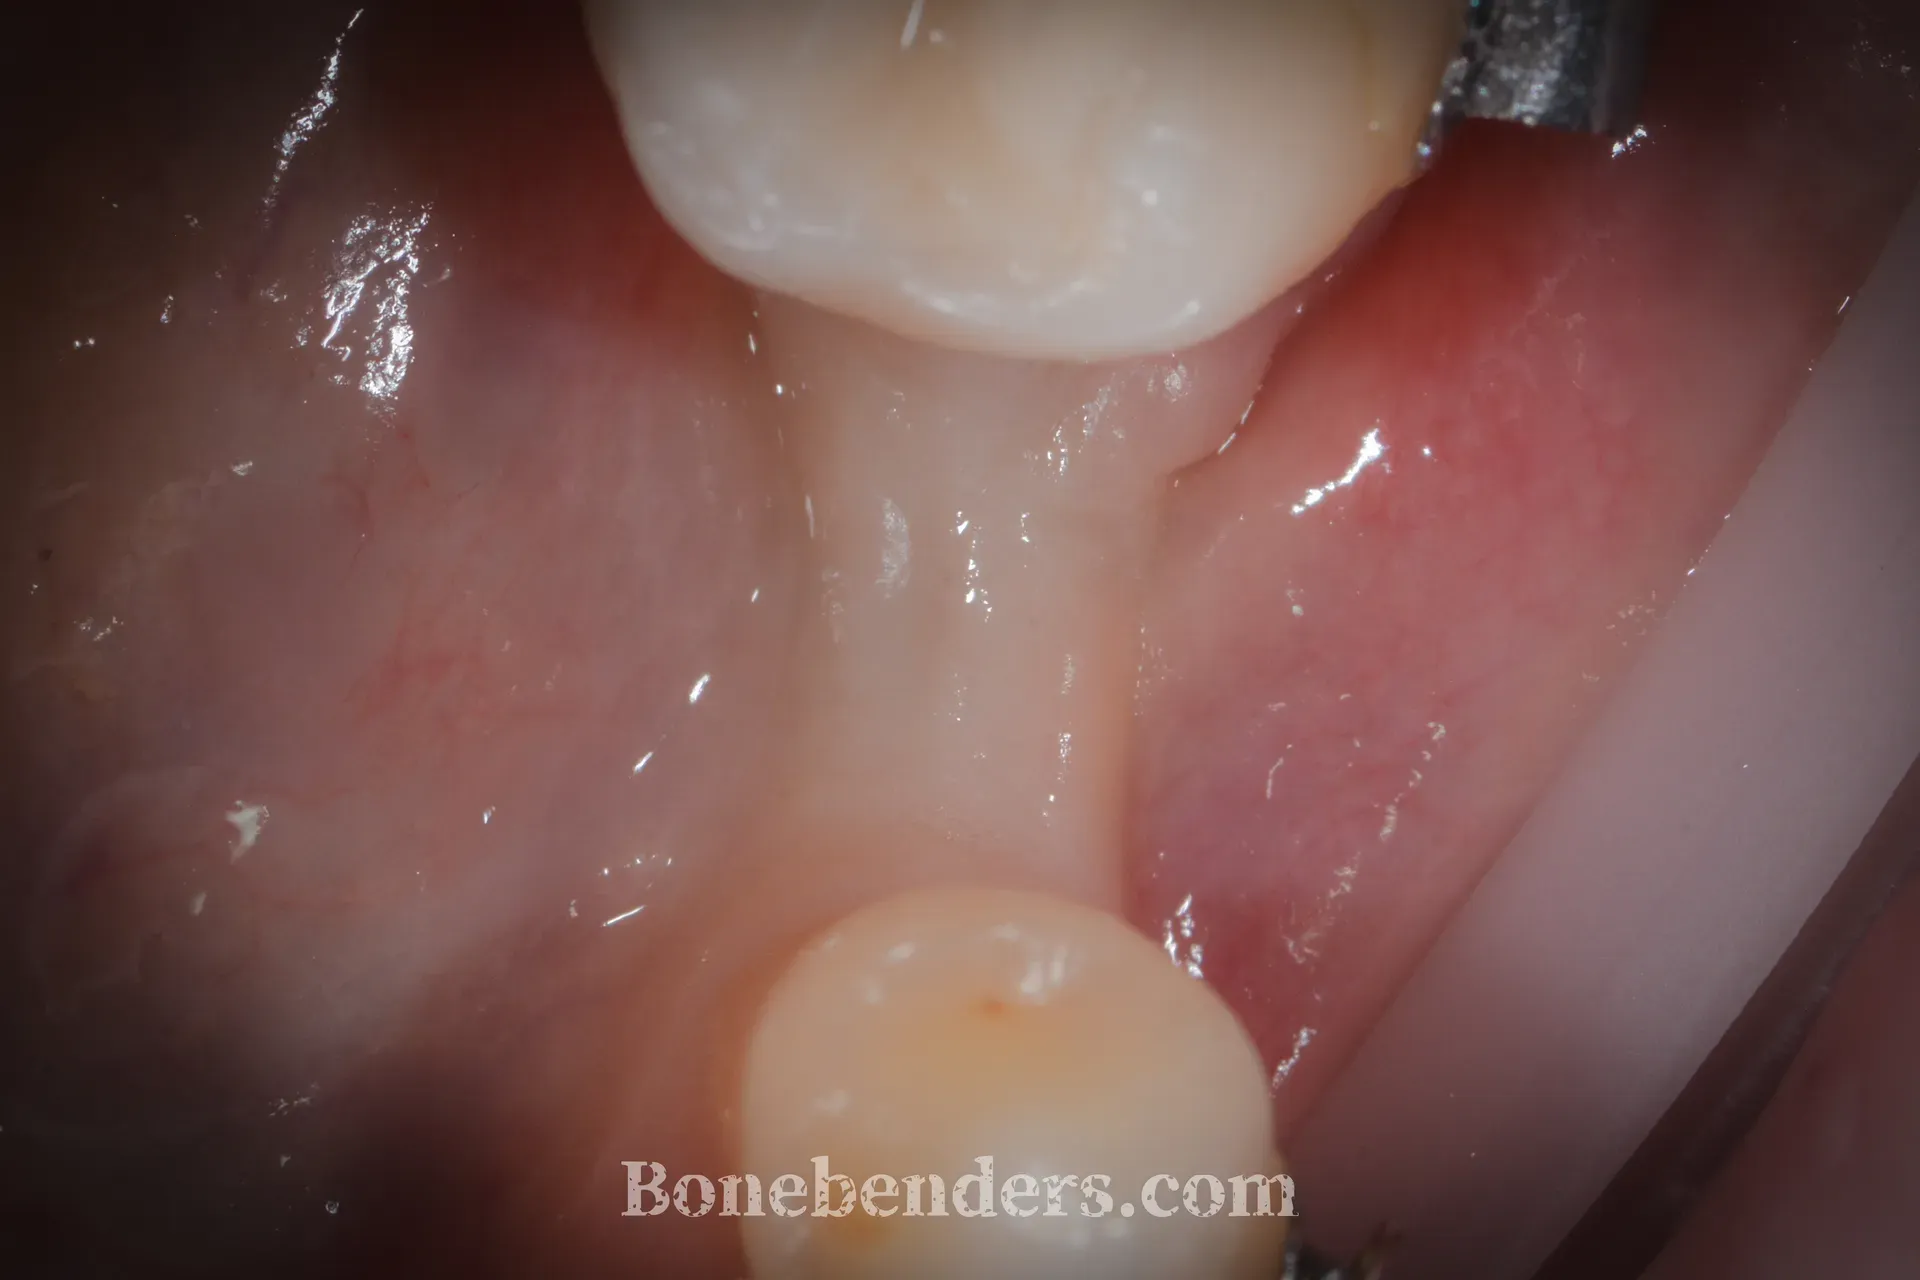

Osteotomia longitudinale della cresta con inserti piezoelettrici. Espansione progressiva con osteotomi calibrati fino a raggiungere uno spessore compatibile con l’inserimento di un impianto. Nessun innesto e guarigione del gap osteomucoso per seconda intenzione.

La corona in ceramica definitiva è in funzione. I tessuti molli periimplantari sono stabili, con sondaggio fisiologico su tutti i versanti. L’estetica è salva.